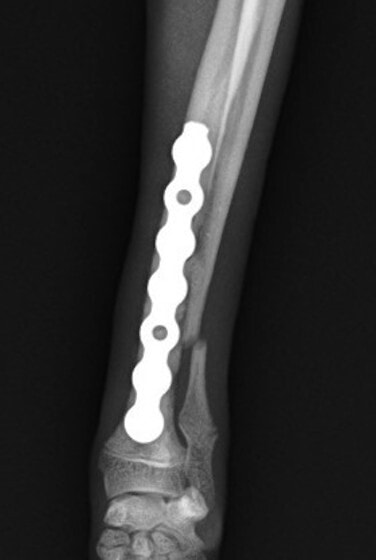

トイプードル 右遠位橈尺骨短斜骨折のALPSによる内固定

当院ではAdvanced Locking plate system(ALPS)と、Locking compression plate system(LCPS)という骨接合法で骨折症例の治療を行っています。

従来型のプレートのように広い面積で骨と接するプレートを用いて固定を行った場合、プレート下の骨はプレートとの接触面において血行が絶たれ壊死し、それがリモデリングされると骨密度が低下する。この骨密度の低下防ぐために、骨折部局所への血行を温存することの重要性が近年改めて認識されるようになってきている。Advaed Locking Plate System (ALPS)は従来型のプレートシステムの欠点を改良し、より使いやすく、より骨への血行を阻害しないようにというコンセプトで作られた。

LCPは、スクリュー(ネジ)とプレート(金属の板)をロックする特殊な構造により骨折部位を固定する新しい世代のプレートシステムです。ひとつのホールでロッキングスクリューとスタンダードスクリューの使用を選択できるユニークな構造をしているため、骨折断端間の圧迫を目的とした従来型プレート固定法に加え、高い角度安定性を有するロッキングスクリューを用いた固定法の選択が可能です。従来のプレートシステムでは困難だった部分の骨折や癒合不全の症例に高い治療効果をもたらします。